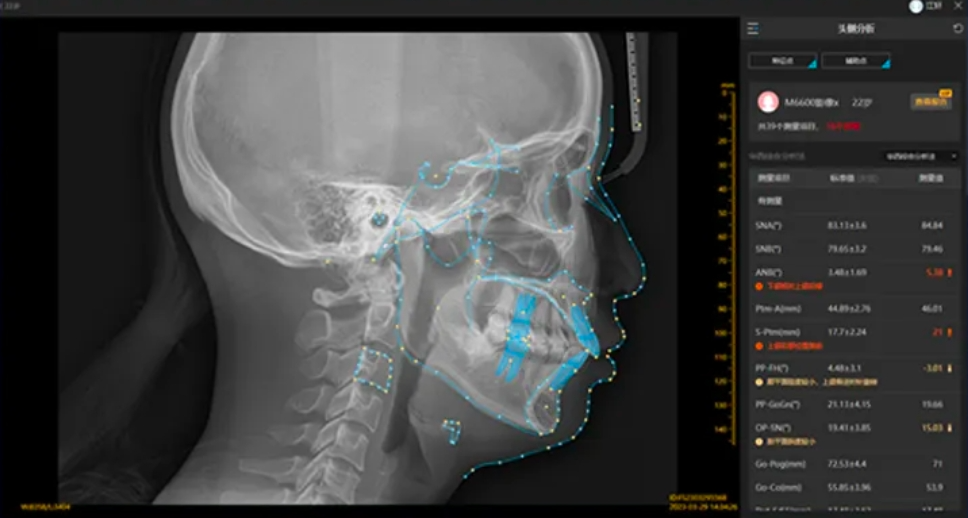

4.协助正畸治疗

CT检查可用于分析错牙合畸形中的骨性、牙性错牙合类型,可以通过测量角度、线距和比例等项目,判断被检者颅面及牙颌面的形态,判断咬合关系,可以用于指导正畸方案的制定,评估正畸效果。